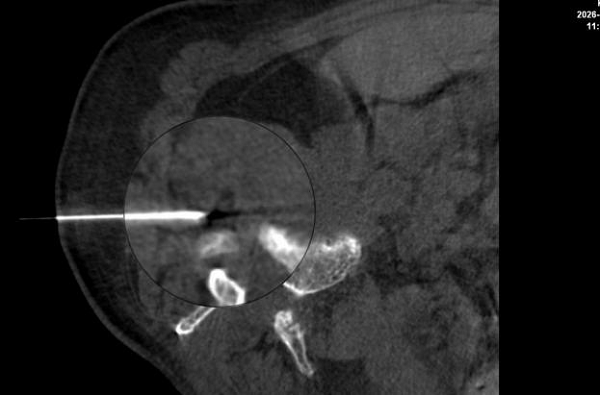

图:医生在影像引导下,精准定位病灶

图:细针穿刺至受压神经根,进行精准给药